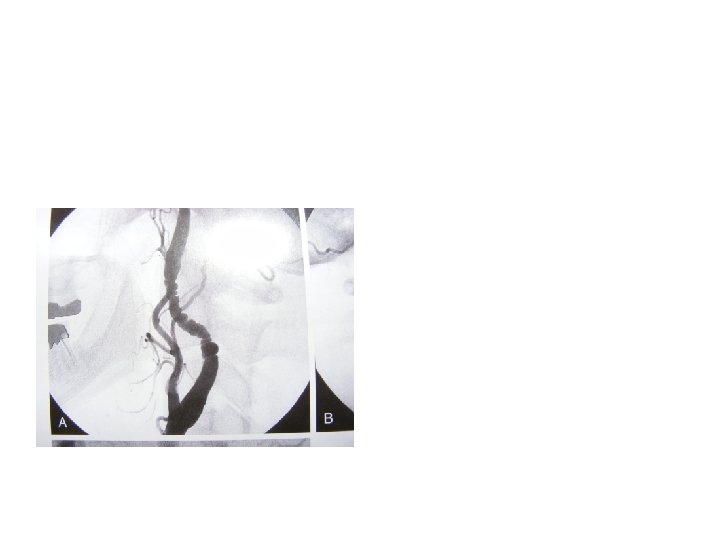

Digital subtraction Karotis anjiografi (DSA) • Altın standard fakat tanıda Şart değil !!!!!! • 3 boyutlu görüntü, darlığın yeri, plak tipi • Cerrahi planlamada yol gösterici • İnvaziv girişim (Hematom, Psödoanevrizma, AVF) • Mortalite • Konrast madde (Nefrotoksik, allerji)